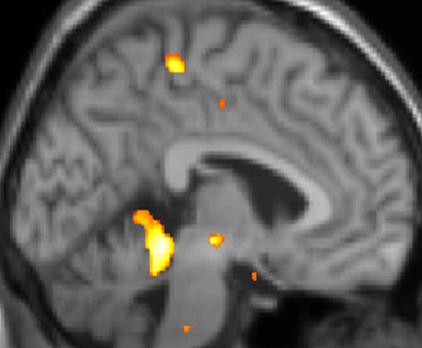

복셀 기반 형태 계측법 이미지 1: 뇌 영역의 구조적 차이

복셀 기반 형태 계측법 이미지 2: 뇌 영역의 구조적 차이

복셀 기반 형태 계측법 이미지 3: 뇌 영역의 구조적 차이

실제로 양전자 방출 단층 촬영술(PET) 스캔 연구 결과, 군발 두통 발작 중에 통증이 없을 때와 비교하여 시상하부의 특정 영역이 활성화되는 것이 관찰되었다. 또한, 복셀 기반 형태 계측법(VBM)을 이용한 연구에서는 군발 두통 환자와 그렇지 않은 사람 사이에 뇌 구조를 비교했을 때, 시상하부의 일부 영역에서 구조적인 차이가 발견되기도 했다.[35] 이러한 영상 연구 결과는 시상하부가 군발 두통의 발생과 관련이 깊다는 가설을 뒷받침한다.

일부 전문가들은 특히 후부 시상하부의 회백질이 군발 두통 발병 기전에 중요한 역할을 할 것으로 보고 있으며, 이 부위에 대한 뇌 심부 자극술 치료가 비교적 높은 성공률을 보이는 것이 이를 뒷받침하는 근거로 제시된다.[3] 또한, 군발 두통의 일중 및 계절적 리듬을 고려할 때, 인체의 주요 생체 시계인 시교차상핵이 시상하부와 함께 관여할 수 있다는 연구 결과도 있다.[34]